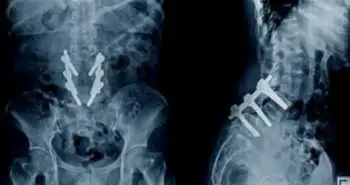

Patients who underwent ACDF had significantly shorter surgery time, lesser blood loss, and decreased hospital stay. Significant increases in JOA scores and decreases in NDI and both neck pain and arm pain VAS scores were observed in both the groups (figure 1), however, patients who undertook PDF had considerably higher NDI scores, neck pain VAS scores, loss of cervical lordosis and ROM. In the ACDF group, 3 patients developed dysphagia, and 2 patients had C5 root palsy and 1 had hematoma in the PDF group.